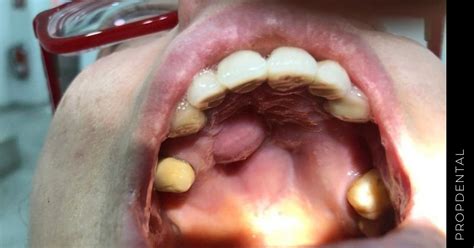

Un bulto en el paladar es una protuberancia o masa que aparece en la parte superior de la boca. Estos bultos pueden tener distintos tamaños, formas y consistencia diferentes, y pueden ser tanto blandos o duros si los presionamos.

Existen distintas trastornos que pueden provocar la aparición de un bulto en el paladar. Puede ser que sin saber cómo ni por qué te aparezca un bulto en el paladar y todavía estés buscando una explicación.